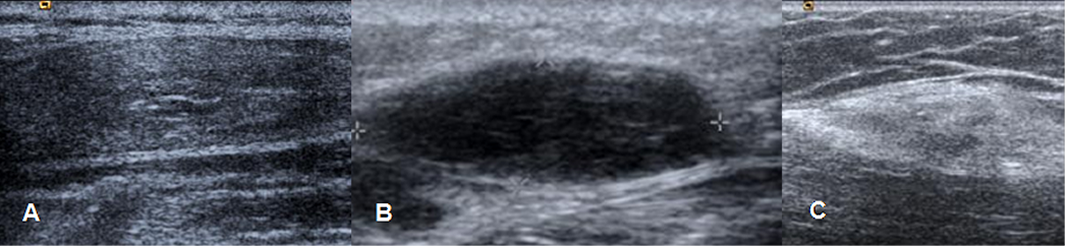

En la ecografía se aprecia como una imagen ovalada y bien definida, iso o hiperecoica con relación a la grasa subcutánea, múltiples estriaciones lineales y con eje mayor paralelo a la piel. (9). (Fig 159).

Fig 159. Lipoma.

A, B y C: Ecografías. Diferente espectro de presentación del lipoma. Imágenes ovaladas isoecoica, hipoecoica o hiperecoica.